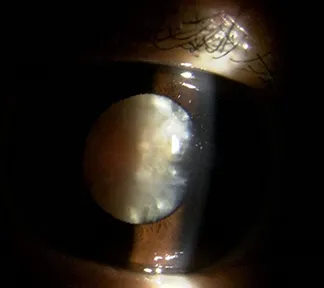

白内障は目の中の水晶体が濁って視力低下を起こす病気です(写真1)。白内障手術はその濁りを取り除き、代わりに人工のレンズを目の中に入れる手術です(写真2)。

また当院では、さまざまな白内障に対応いたします。下にお示しする症例は、非常に進行した白内障の手術前後の写真です。